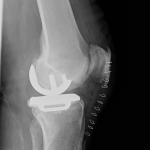

PRACHATICE – Na ortopedickém oddělení Nemocnice Prachatice byl minulý týden proveden unikátní výkon – implantace oboustranné částečné náhrady kolenního kloubu. Jde o málo frekventovaný typ operace, který se provádí jen na menším počtu ortoepedických pracovišť v České republice.

Unikondylární náhrada představuje šetrnější variantu totální endoprotézy – nahrazuje pouze poškozenou část kolenního kloubu, zatímco zbytek zůstává zachován. Aby pacient z operace skutečně profitoval, je nutné splnění indikačních kritérií, která lze shrnout do několika bodů: artrotické postižení jedné poloviny kloubu a dobrý stav té druhé, funkční vazy, dobrý rozsah pohybu, nepřítomnost výrazné deformity.

S oboustrannými implantacemi totálních endoprotéz mají v prachatické nemocnici již několikaleté zkušenosti. Nyní však poprvé provedli dvojitou operaci částečné náhrady. Zásadní je přitom nejen zvládnutá operační technika, ale i souhra celého týmu, díky které je pacient schopen se již v prvních hodinách po výkonu postavit, operované klouby zatížit a relativně bezbolestně zvládat rehabilitaci.